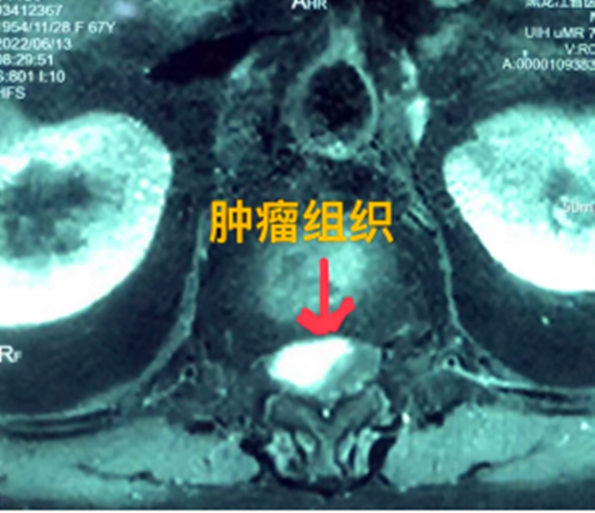

據(jù)省醫(yī)院神經(jīng)外一科陶宇醫(yī)生介紹,家住外地的張大娘最近總感覺雙下肢疼痛、無力,且排尿困難及便秘,伴有行走困難。時間長了,張大娘病情逐漸加重,劇烈的疼痛甚至讓她無法完整入睡。在當?shù)蒯t(yī)院,張大娘按腰椎肩盤突出接受治療,但未見好轉(zhuǎn),隨后進行的胸椎MRI(核磁共振)檢查,結(jié)果不禁讓張大娘和家屬瞠目結(jié)舌,原來張大娘患的竟然是少見的脊髓腫瘤。

張大娘住進了黑龍江省醫(yī)院神經(jīng)外一科,該科孫國章主任醫(yī)師熱情地接待了張大娘,并邀請骨外一科專家共同為她進行了聯(lián)合會診。發(fā)現(xiàn)張大娘病情十分復雜棘手,脊髓腫瘤體積較大,充滿髓腔且神經(jīng)已經(jīng)完全受壓,需要手術(shù)來完整切除。同時還發(fā)現(xiàn)張大娘的胸腰部曾受過兩次外傷,伴有多處骨折,這對接下來的手術(shù)操作帶來一定影響。